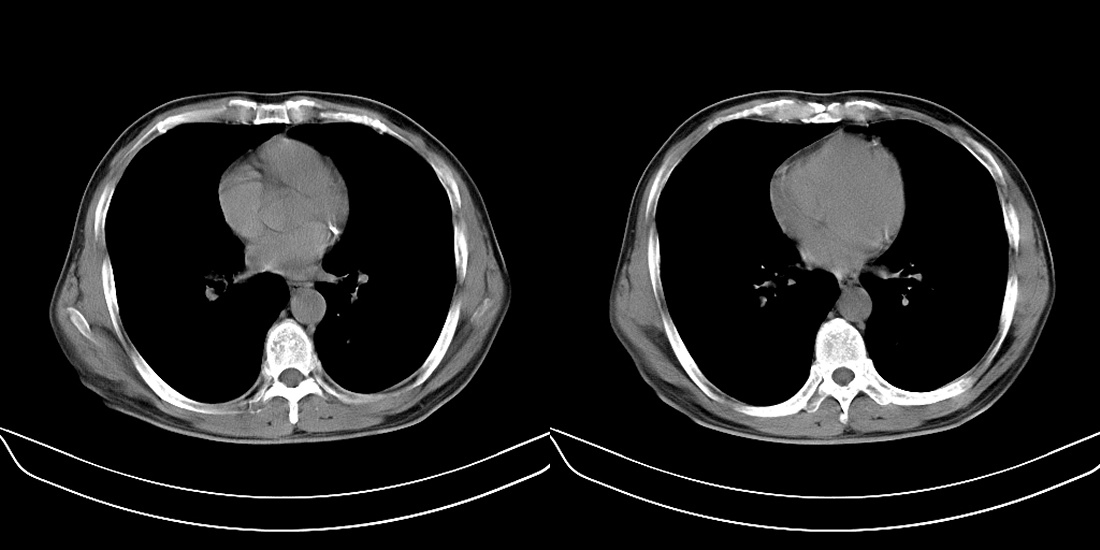

标题: CT10251:男性56岁,结核球? [打印本页]

标题: CT10251:男性56岁,结核球?

56岁男性,低热、消瘦,曾x线诊断肺结核。

两肺结核,左肺结核球。

双肺结核伴左上肺结核球形成

两肺多形性病变,支持肺结核.

两肺多形性病变,且在结核好发部位。支持肺结核.